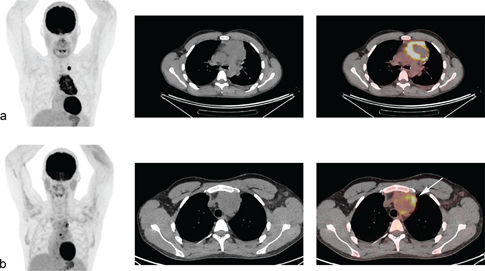

Fig 5

Figure 5. Metabolic tumor volume measurements with volume delineation using the SUV41% thresholding method (a) and SUV2.5 thresholding method (b). The total metabolic tumor volume (including all the lesions) was 91ml with the 41%SUVmax method vs 250ml with SUV>2.5.